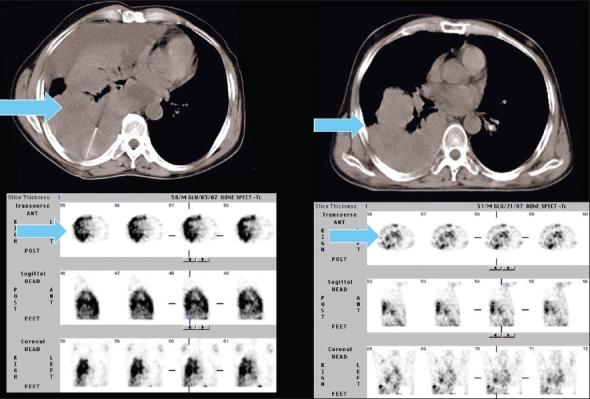

Several radiotracers have been used for assessing cell death, whether by necrosis or apoptosis. (99m)Tc glucarate, which has initially been reported to be concentrating/accumulating in myocardial infarction or zones of cerebral injury, has also shown some tumor-seeking properties in a few preliminary studies. Under International Atomic Energy Agency (IAEA)'s coordinated research program, we report here the standardization, quality control, and clinical evaluation (detection, evaluation of response, and comparison with (18)F Fluorodeoxyglucose) of this tracer in well-characterized lung cancer and head neck malignancies in a single-arm prospective observational study. Forty-seven patients (29 inoperable lung carcinoma and 18 head and neck malignancies) were prospectively enrolled and underwent (99m)Tc glucarate imaging [whole body planar and single-photon emission computed tomography of the region of interest] 4-5 hours after injection of 20 mCi of the radiopharmaceutical. Excellent (99m)Tc glucarate concentration was noted in the target lesion in lung cancer and head and neck malignancies. The sensitivity was found to be better in lung cancer. Avid concentration of tracer was seen in the metastatic sites. During response evaluation, the glucarate concentration correlated well with the clinical and other radiological findings. (99m)Tc glucarate showed avid concentration of tracer in the tumor, suggesting it to be a potential tumor imaging agent which can be used for detection and assessment of therapeutic response in malignancy.

几种放射性示踪剂已被用于评估细胞死亡,无论是坏死还是凋亡。(99m)锝葡糖醛酸,最初据报道其在心肌梗死或脑损伤区域浓聚/蓄积,在一些初步研究中也显示出一定的肿瘤摄取特性。在国际原子能机构(IAEA)的协调研究项目下,我们在此报告在一项单臂前瞻性观察研究中,对这种示踪剂在特征明确的肺癌和头颈部恶性肿瘤中的标准化、质量控制及临床评估(检测、反应评估以及与(18)F氟脱氧葡萄糖比较)。47例患者(29例不可手术的肺癌和18例头颈部恶性肿瘤)被前瞻性纳入研究,并在注射20毫居里放射性药物后4至5小时接受(99m)锝葡糖醛酸显像[全身平面显像及感兴趣区域的单光子发射计算机断层扫描]。在肺癌和头颈部恶性肿瘤的靶病变中观察到(99m)锝葡糖醛酸的良好浓聚。发现其在肺癌中的敏感性更好。在转移部位可见示踪剂的摄取。在反应评估期间,葡糖醛酸浓度与临床及其他影像学结果相关性良好。(99m)锝葡糖醛酸在肿瘤中显示出示踪剂的摄取,表明它是一种潜在的肿瘤显像剂,可用于恶性肿瘤的检测和治疗反应评估。